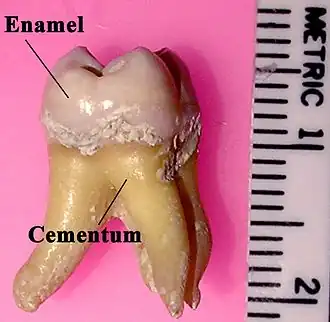

Labeled molar | |

Tooth enamel is one of the four major tissues that make up the tooth in humans and many animals, including some species of fish. It makes up the normally visible part of the tooth, covering the crown. The other major tissues are dentin, cementum, and dental pulp. It is a very hard, white to off-white, highly mineralised substance that acts as a barrier to protect the tooth but can become susceptible to degradation, especially by acids from food and drink. In rare circumstances enamel fails to form, leaving the underlying dentin exposed on the surface.[1]

In humans, enamel varies in thickness over the surface of the tooth, often thickest at the cusp, up to 2.5 mm, and thinnest at its border with the cementum at the cementoenamel junction (CEJ).[5]